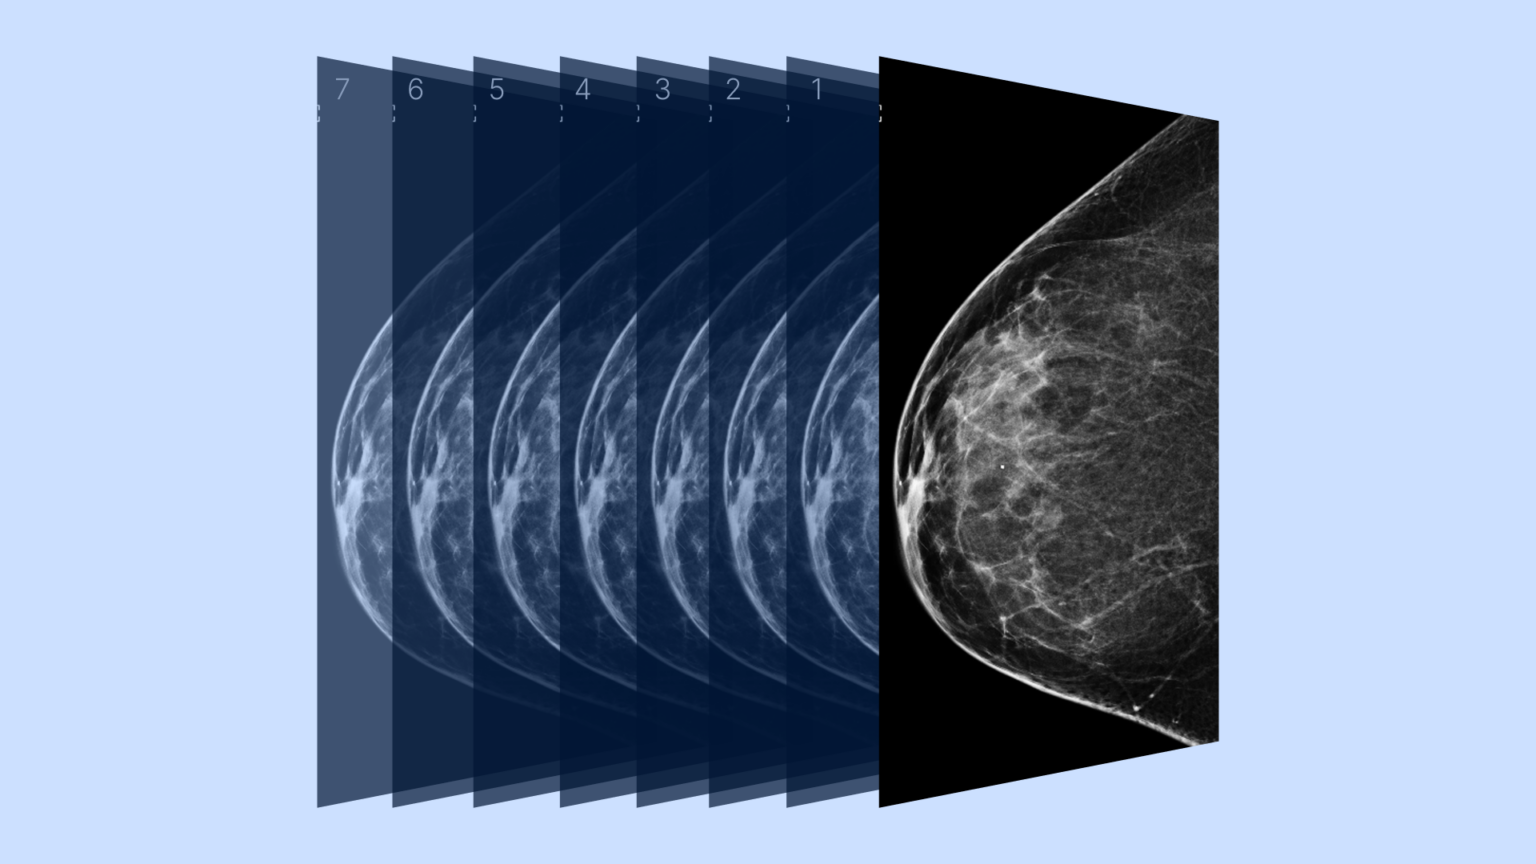

The 3D mammogram on the right shows the breast cancer much better than Is 3D Imaging Better For Mammogram I recommend 3d mammograms for all women, the breast. Among the pros, it can better detect signs of cancer (especially in dense breasts) and reduce the likelihood of repeat imaging. How often should i be screened? Digital mammograms use electronic technology to capture and store breast images. When combined with a standard mammogram, 3d mammograms may detect more cancers than. Is 3D Imaging Better For Mammogram.